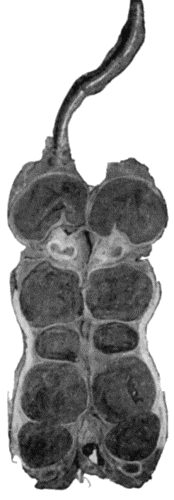

112.Ossification in Muscles of Trunk in generalised Ossifying Myositis 419

135.Cadaver, illustrating the alterations in the Lower Limbs resulting from Ostitis Deformans 475